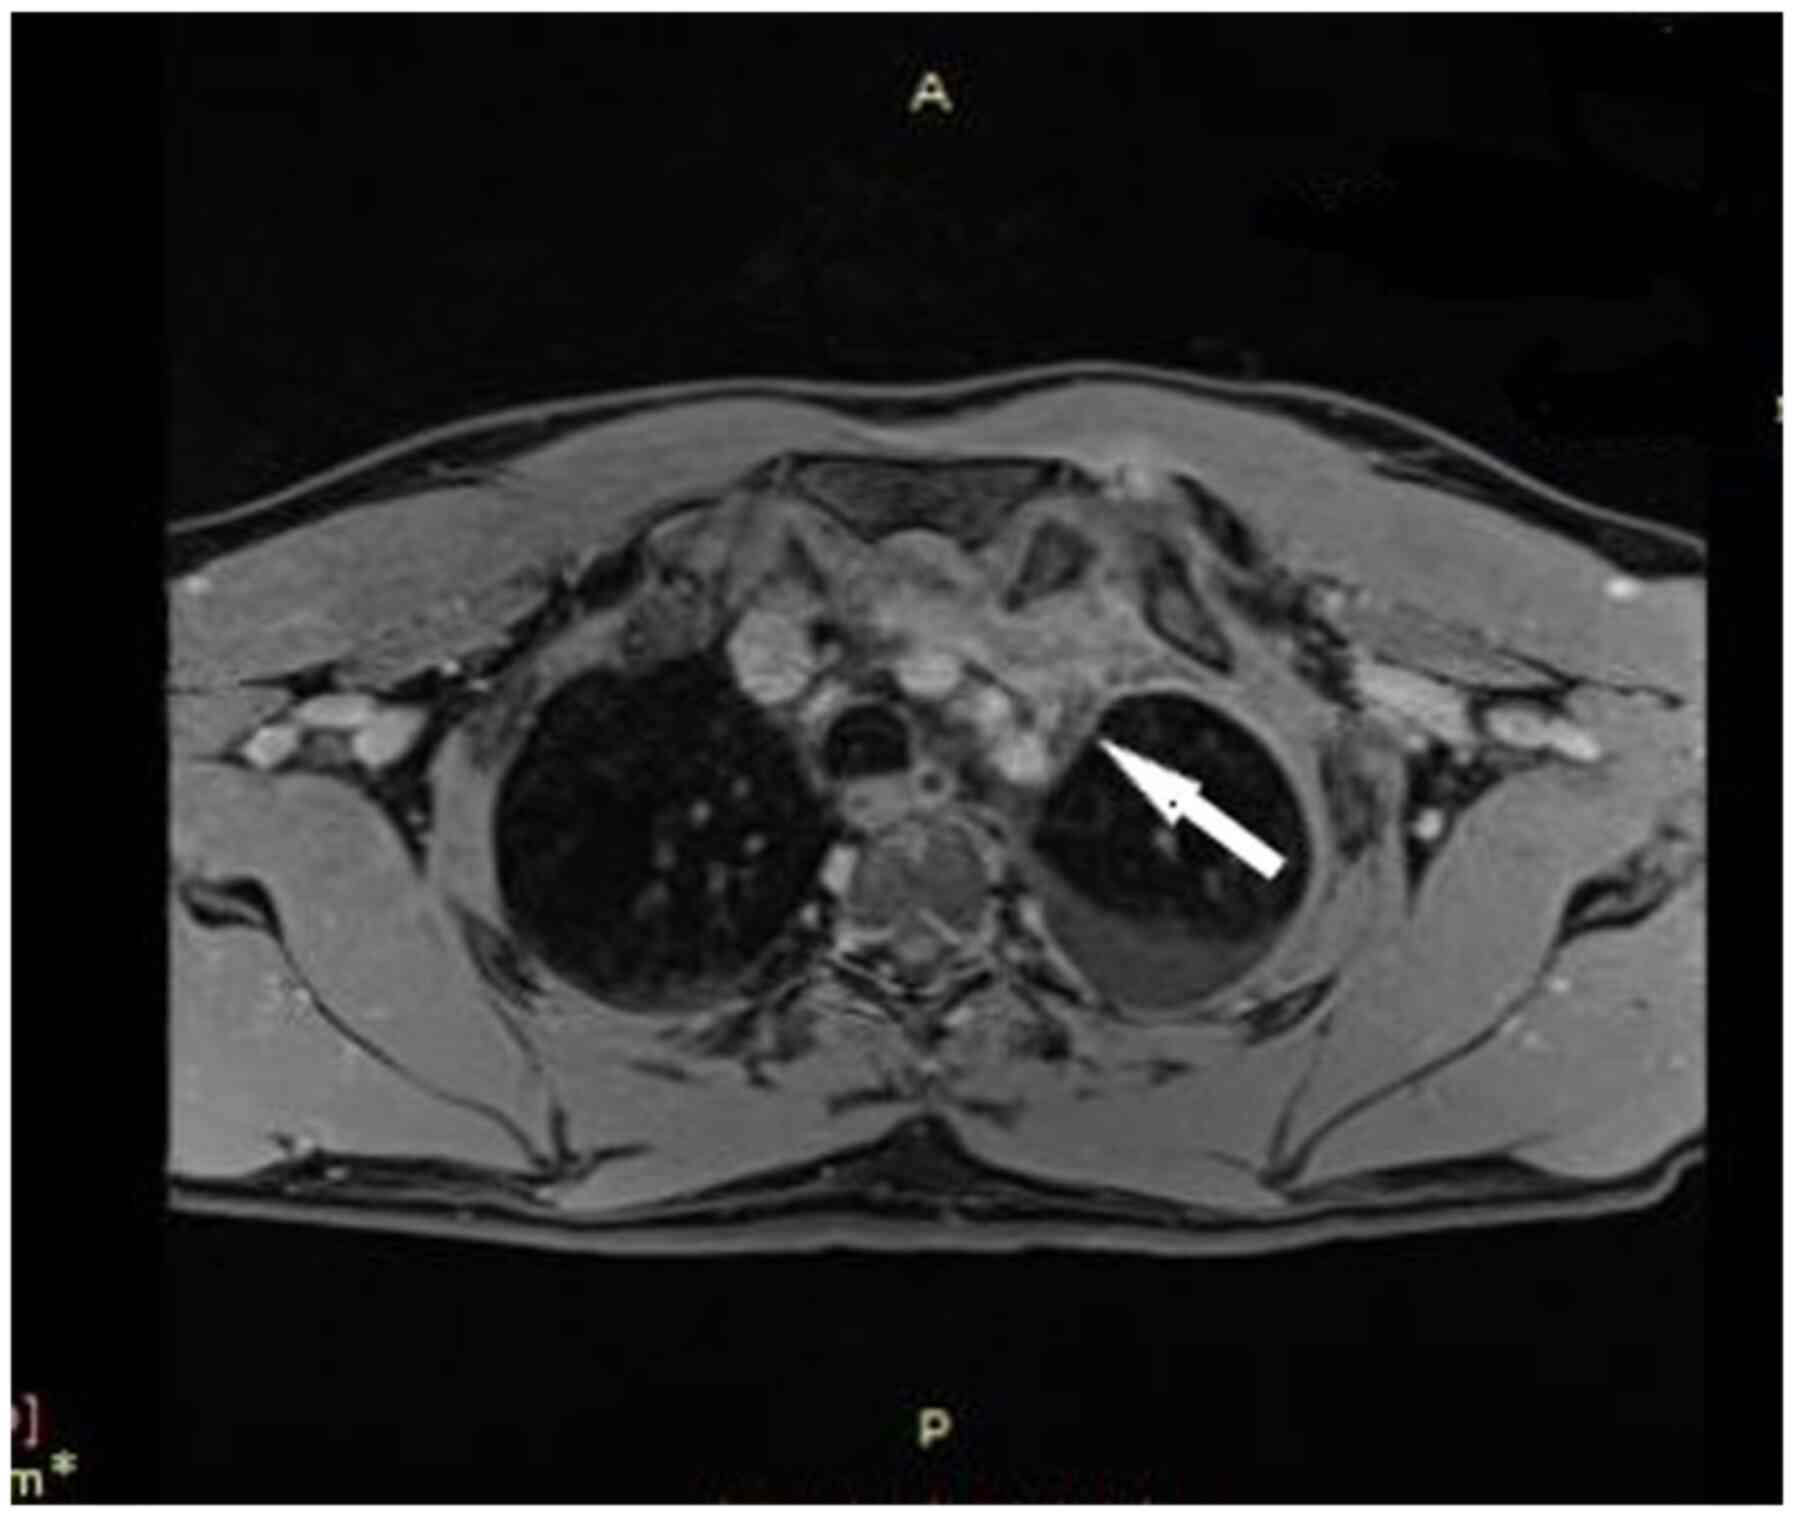

The patient underwent computed tomography (CT) of the chest showing consolidation in the left lower lobe with left pleural effusion, edema of the soft tissue adjacent to the first sternocostal joint and heterogeneity, and invasion of the retrosternal fat (Figs. 2 and 3). In addition, the patient underwent magnetic resonance imaging (MRI) of the chest, to obtain detailed information regarding the pleura and mediastinum, that revealed abnormal soft tissue with dimensions at transverse level 7.0x1.3 cm, containing cystic lesions, adjacent to the first sternocostal joint, indicating inflammation in sternocostal cartilage. MRI also revealed contrast enhancement of the ipsilateral mediastinal pleura, imaging compatible with mediastinitis (Fig. 4).

Figure 4

Magnetic Resonance Imaging of the chest shows a large abnormal soft tissue containing cystic lesions, adjacent to the first sternocostal joint. A, anterior; P, posterior.